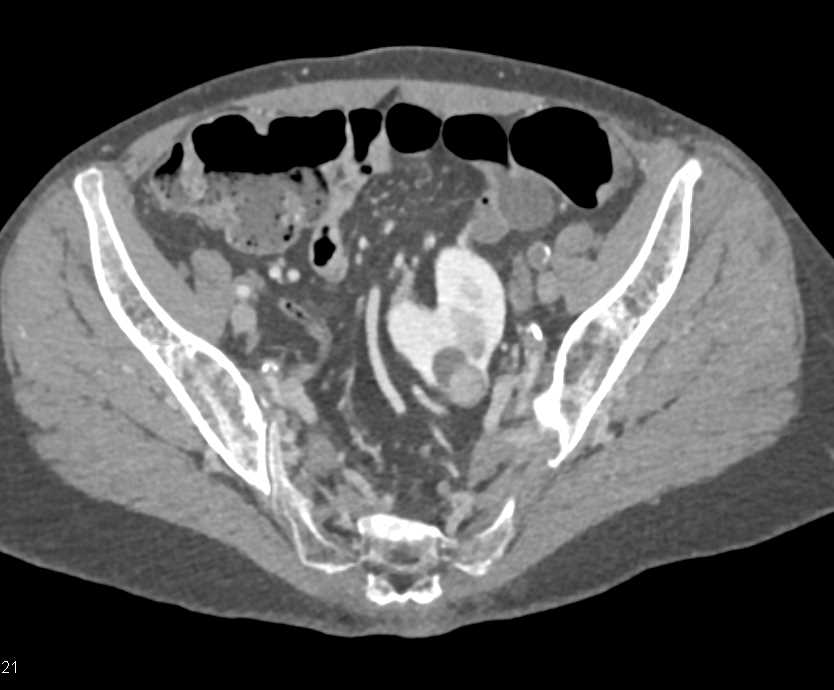

Renal Cell Carcinoma is a Solid Mass